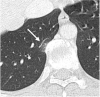

Fig. 13

HRCT demonstrates subpleural basal reticulations in a never-smoker 78-year-old man (arrows) (A). Axial image in a 67-year-old man with a diagnosis of idiopathic pulmonary fibrosis shows diffuse irregular septal thickening, traction bronchiectasis, and honeycombing (B)